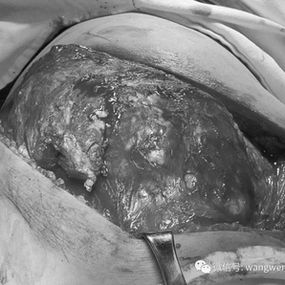

There is a large tumor on the right chest wall, with dimensions of approximately 30x25x20 cm. It is firm, tender to the touch, and has limited mobility. The tumor has already involved the 5th through 8th ribs on the right side.

1. An incision was made on the right posterior chest wall to expose the tumor, which was then resected along with the affected ribs.

Related Photos